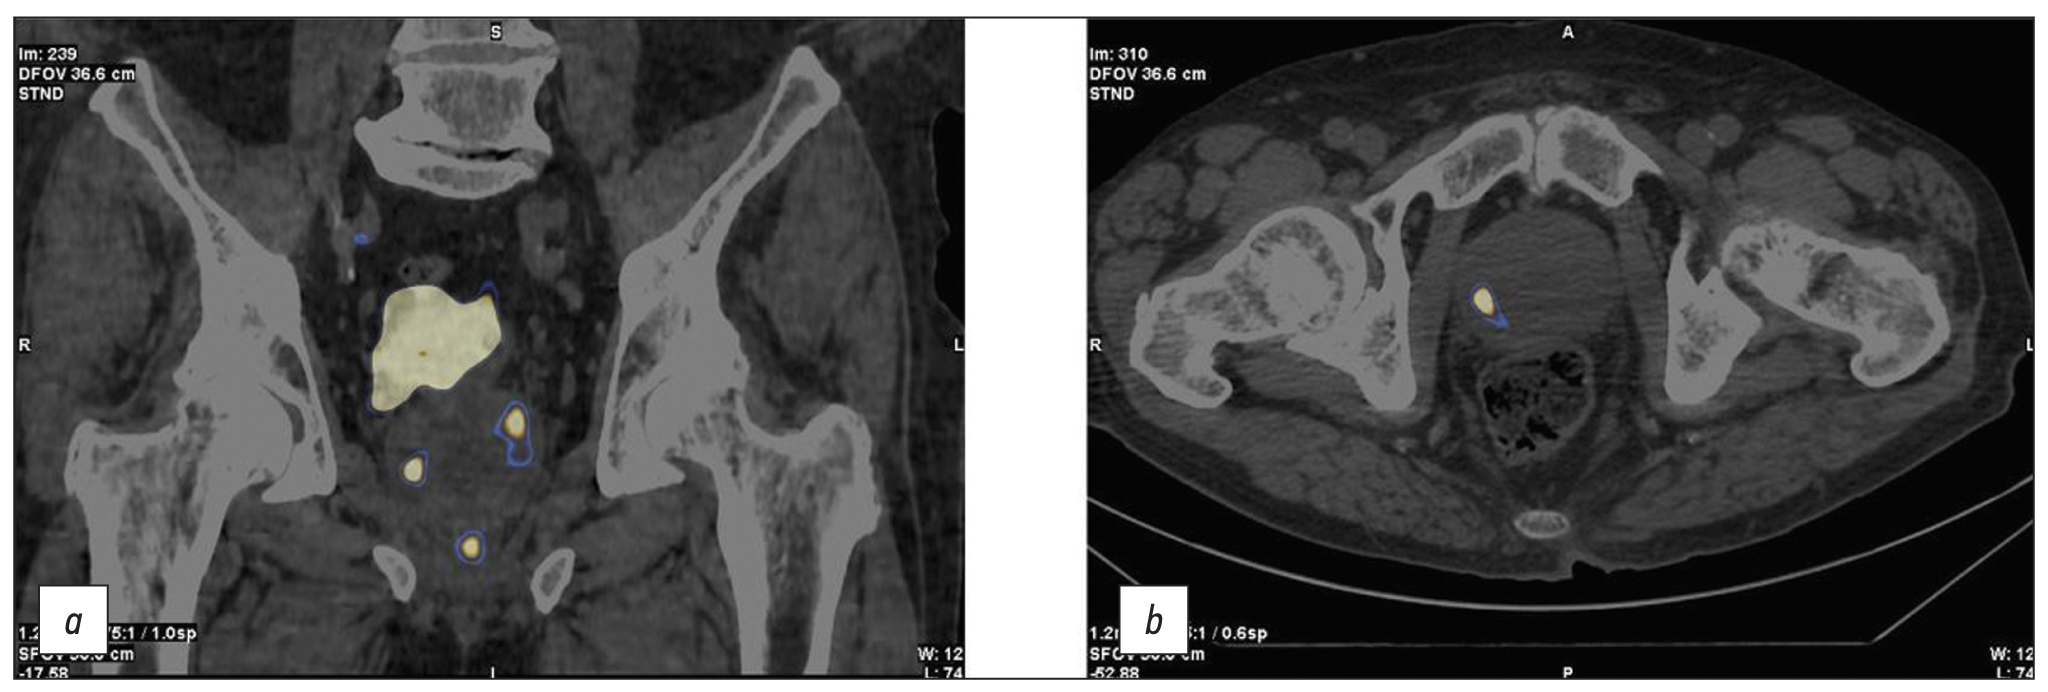

Patient K., 73 years old, was admitted with diffuse prostatic hyperplasia, urinary retention, an epicystostomy, and a 12.7-ng/mL PSA. A multisite biopsy performed under US guide revealed no evidence of malignant development. SPECT/CT data with 99mTc-HYNIC-PSMA are shown in Figure 4. SPECT/CT revealed a 14-mm3 site of RP accumulation in the prostate tissue. A CT-guided targeted biopsy was performed using pararectal access. A morphological diagnosis was adenocarcinoma, Gleason 6 (3 + 3).

Fig. 4. Patient K., 73 years old, SPECT /CT with 99mTc-HYNIC-PSMA, (a) frontal and (b) axial sections: Sites of radiopharmaceutical accumulation in the anterior part of the transition zone in the apex of the right lobe, posterolateral part of the peripheral zone at the level of the base of the left lobe, and posterolateral part of the peripheral zones at the level of the base and middle third of the left lobe of the prostate gland; physiological accumulation of radiopharmaceuticals in the bladder.

On November 28, 2020, CT-guided focal implantation of 125I sources was performed pararectally. Transurethral resection of the intravesical component was performed, and the epicystostomy was removed. The follow-up examination (November 28, 2022) showed a PSA level of 0.13 ng/mL, spontaneous urination, and 15-cm3 residual urine.

In this case, problems were as follows: inability to identify the cause of elevated PSA, a “large” volume of the prostate gland, and epicystostomy. Considering data on RP accumulation patterns and biopsy results, we were unable to successfully solve these problems and perform successful focal brachytherapy using a hybrid diagnostic use of RP CT-guided biopsy.